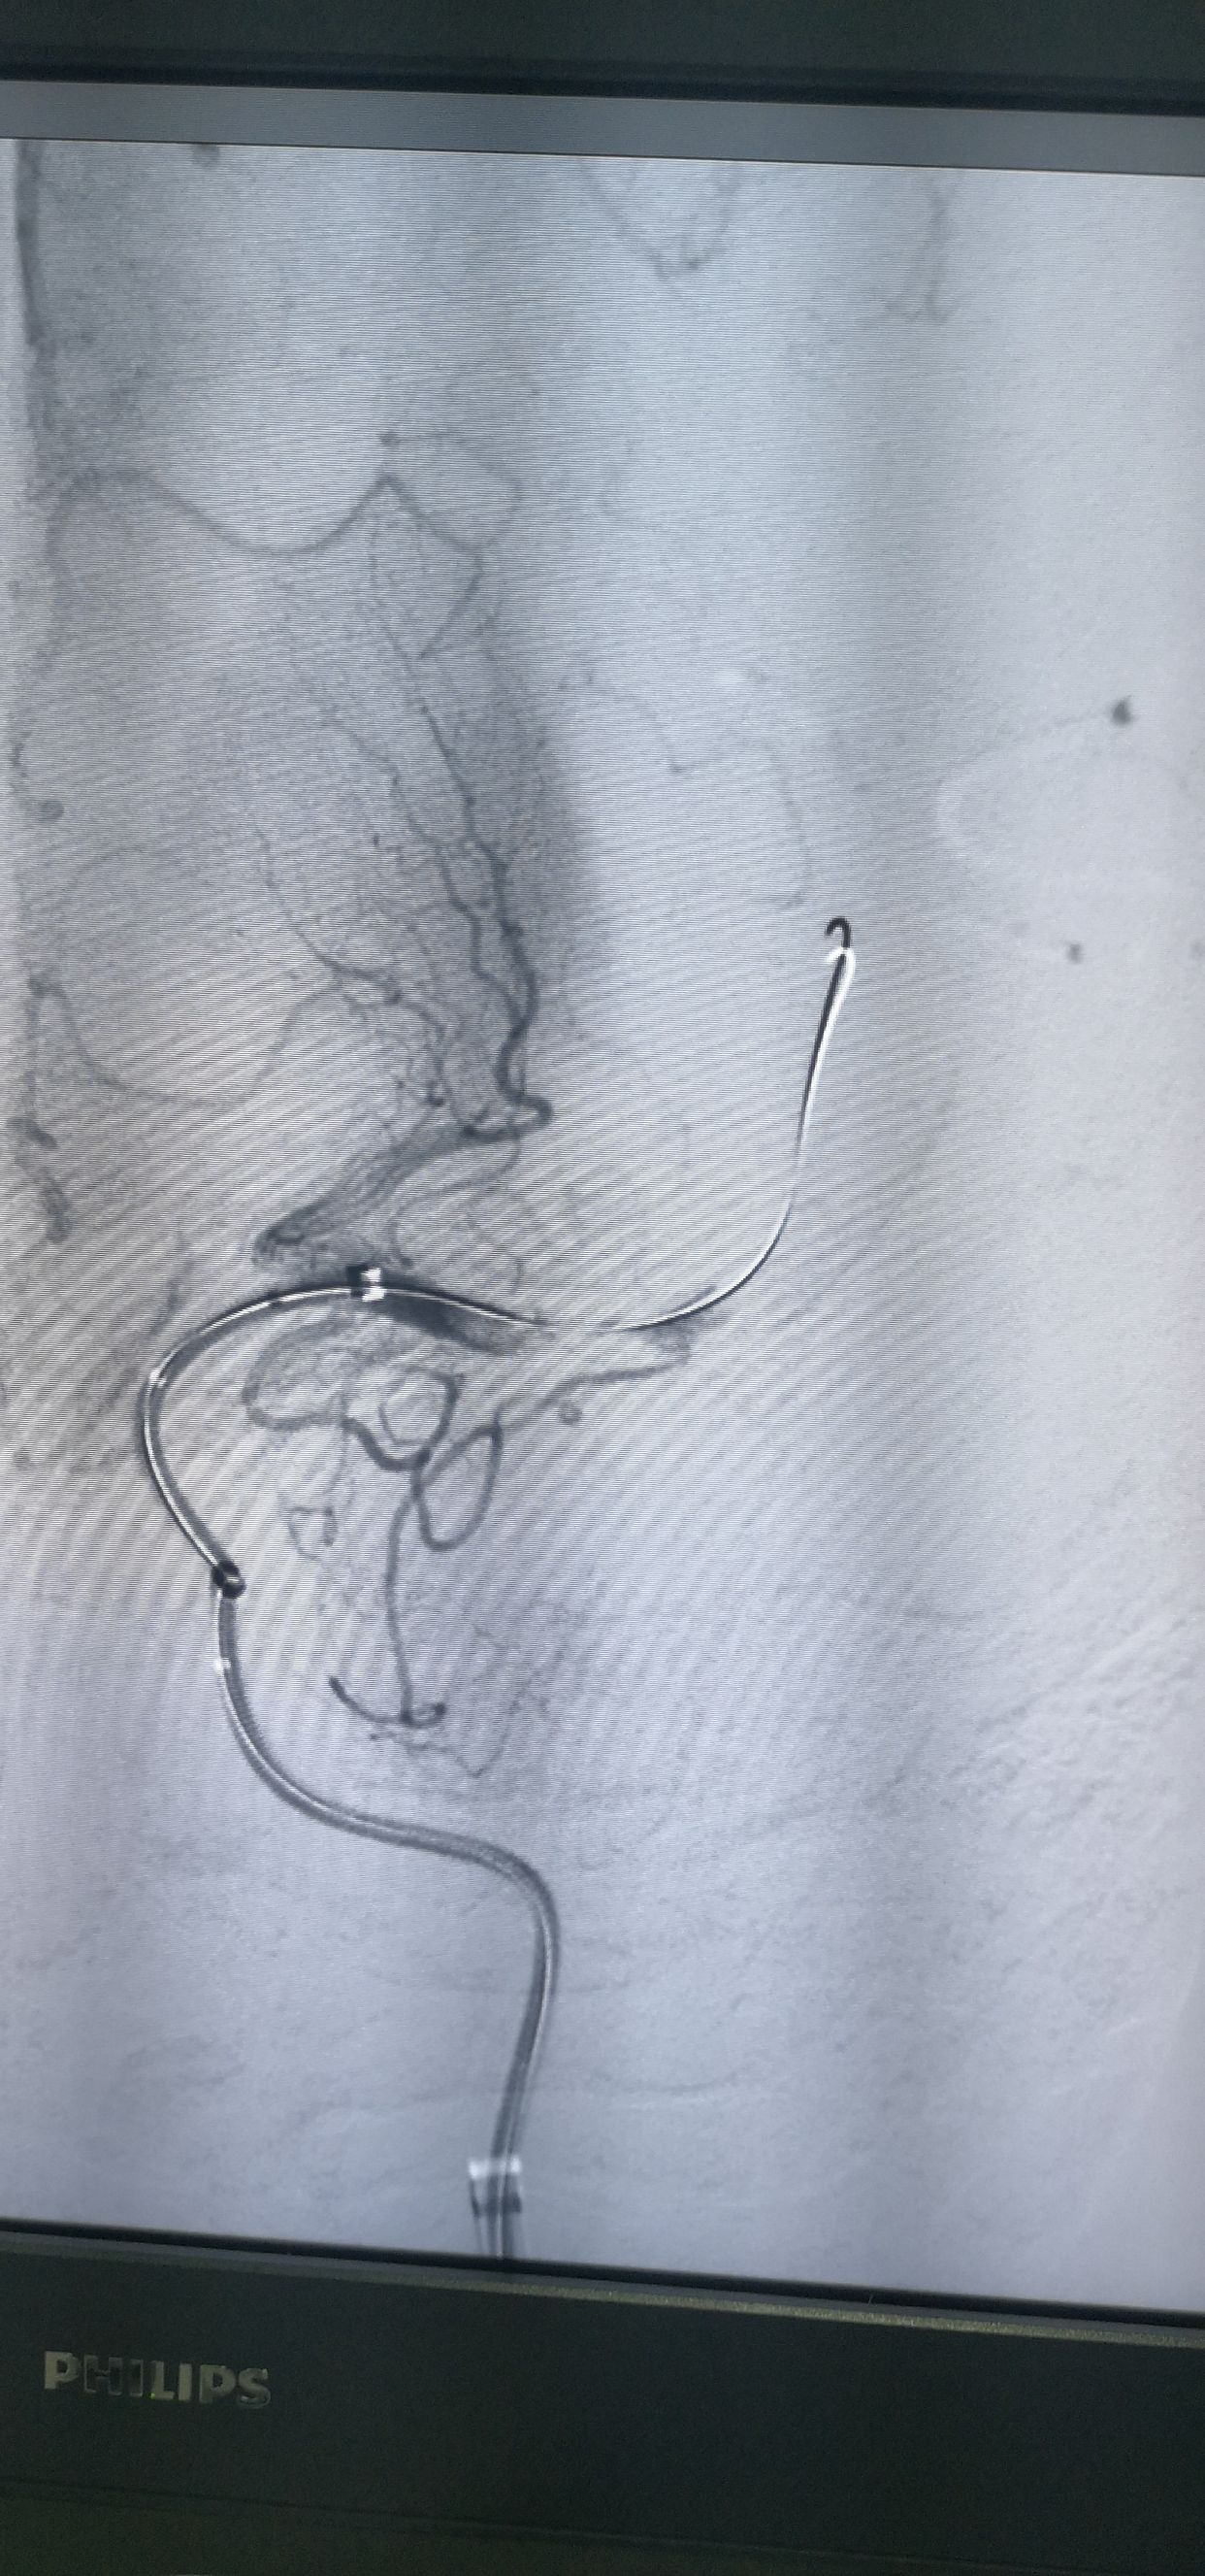

支架释放

释放支架后造影,提示有下干充盈缺损

支架配合抽吸导管取栓

取出栓子

◆ 整体支架的推送,释放和回撤更加简单,轻松和快捷;

◆ 由于支架体有效工作段增加了12个铂金显影标记点,在术中透视的观察清晰直观,能实时获得手术反馈的动态。例如,支架释放操作时,微导管回撤到第2组铂金标记点时,我们观察到后续支架的位置和形态均很稳定。由于铂金显影点是环绕在开放卷曲的支架体,两者的设计相加也提示显影所提供的术中反馈是准确且稳定的。

◆ 更为重要的是,支架工作长度更长(40mm),在SWIM技术的运用上也具备以下优势:

1)提供更好的支架锚定效果;

2)在ICA虹吸部可更好地和Navien 导管形成同轴效应;

3)精准定位结合更长支架,实现大负荷量血栓的抓取,实现一次三级开通。